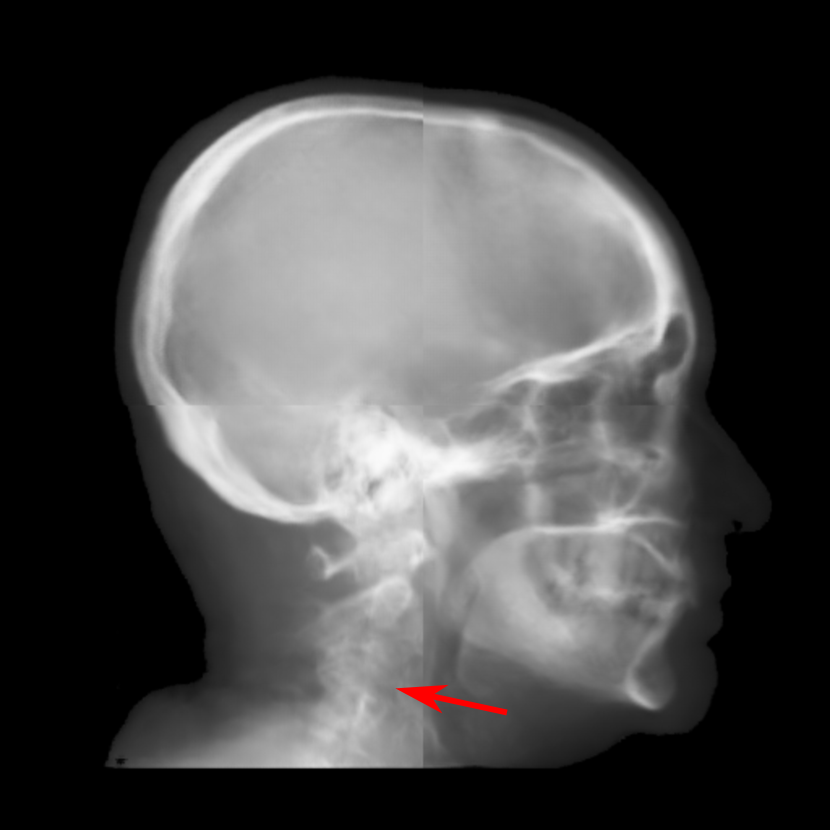

Fig. 10: Synthetic cephalogram examples from 2D CBCT projections. The top two rows are two patches respectively, while the bottom row is a complete stitched cephalogram. In the top row, the blue curve is the outline of the target patch, while the red and green curves are the outlines for the 0superscript00^{\circ} and 180superscript180180^{\circ} projections, respectively. In the middle row, the cranial sutures indicated by the arrow in (j) are not visible in (k) nor in (l); the sella turcica indicated by the arrow in (k) is distorted. In the bottom row, the vertebrae indicated by the arrow in (r) are more accurate than those in (q). The line in (m) marks the position for line profiles in Fig. 12. For the 1-projection output and the 2-projection output, the RMSE (left), PSNR (mid) and SSIM (right) values w. r. t. the target are displayed in the corresponding subcaptions.

The cephalogram synthesis results of two patches and one complete stitched cephalogram are displayed in Fig. 10. In the top row, the blue curve is the outline of the target patch, while the red and green curves are the outlines for the 0superscript00^{\circ} and 180superscript180180^{\circ} projections, respectively. Consistent with the relationship in Fig. 4, the blue curve is between the red and green curves. Since the 180superscript180180^{\circ} projection (green channel) has larger area than the 0superscript00^{\circ} projection (red and blue channels), the region near the boundary appears green in the RGB input patch in Fig. 10(c). Fig. 10(d) is the target output. Fig. 10(e) is the output using the 0superscript00^{\circ} projection only, where the outline has large deviation from the target blue curve. In contrast, in Fig. 10(f) where the dual projections are used, the outline is closer to the target blue curve. In the middle row, the sella turcica in the 1-projection output has large distortion, as indicated by the arrow in Fig. 10(k), compared with that in the target patch. On the contrary, the sella turcica in the 2-projection output (Fig. 10(l)) preserves its shape. These observations highly demonstrate the benefit of using dual projections.